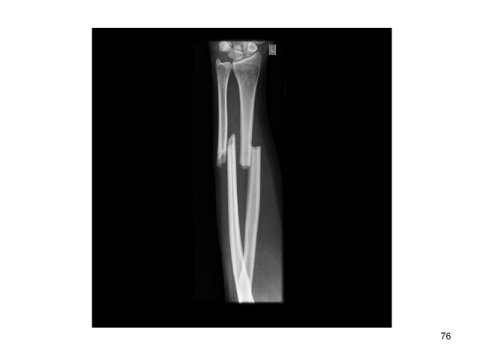

Page 76 - 6. care of client with fracture